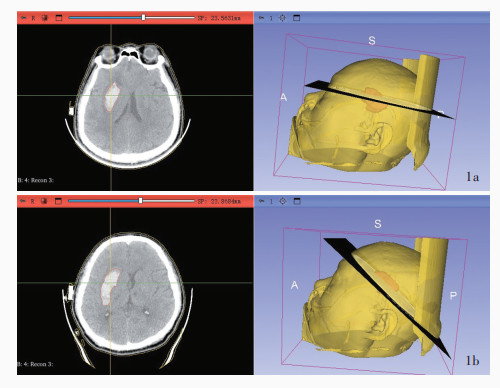

Xu HZ , Guo J , Wang C , Liu X , Song ZQ , Chen RF , Qiu B , Wang Q , Huang Y . A novel stereotactic aspiration technique for intracerebral hemorrhage. World Neurosurg, 2023, 170: e28- e36.

doi: 10.1016/j.wneu.2022.10.051